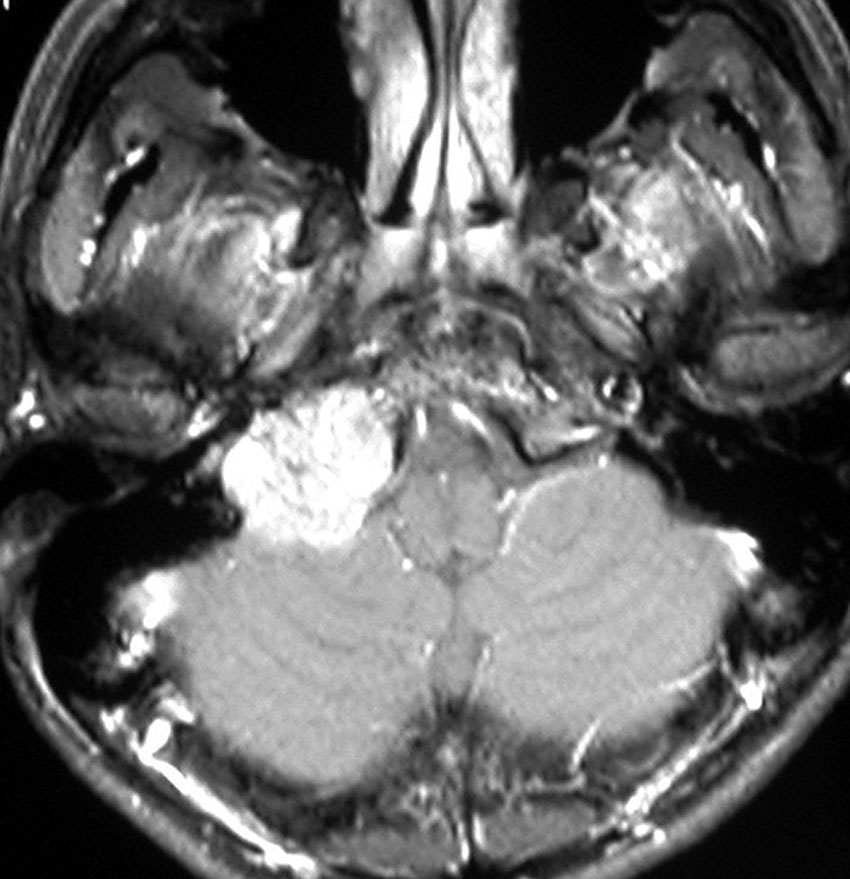

- クラスDでは,頚静脈孔から小脳延髄角部に腫瘍が伸びて,延髄を圧迫して,椎骨動脈系から腫瘍動脈を引き込みます

耳の聞こえと飲み込みが悪くなって発症(難聴と嚥下障害)した20代の患者さんのグロームス腫瘍 jugular paragangliomaです。左の頚動脈撮影 CAGでは,頸部の腫瘍におされて内頚動脈が前方に屈曲しています。外頚動脈から多くの血管が流入して血管腫のように濃い腫瘍陰影がみえます。右側の椎骨動脈撮影 VAGでは,頚静脈孔から頭蓋内の小脳延髄角部まで伸びた腫瘍が染まります。頭蓋内はPICAから頸静脈球と頸部には椎骨動脈の筋肉枝からの腫瘍血管がみられます。

頸部から頸静脈球を抜けてS上静脈洞内に入ります。これはクラスCかDか迷うところです。ちょっと難しい。またこのサイズでは,迷走神経と舌咽神経の機能を温存することができません。延髄方向へ伸展していますし年齢が若いので手術せざるを得ないものでした。